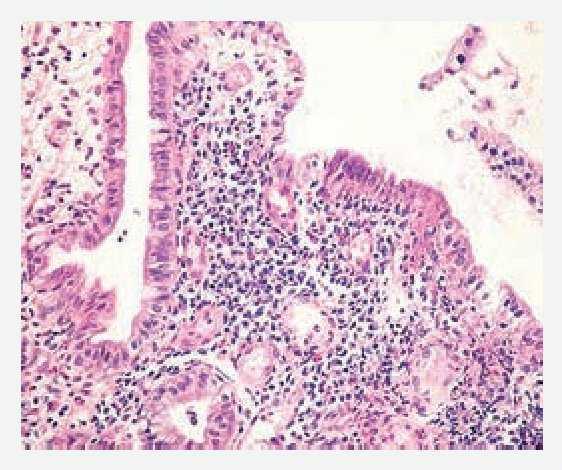

médico conservador. Acudió a consulta por presentar nuevamente dolor en mesogastrio intenso, de 8 horas de evolución, acompañado de vómito de contenido gastrobiliar y distensión abdominal importante. Se le realizó placa simple de abdomen la cual mostró niveles hidroaéreos con dilatación de asas de intestino delgado. Una vez resuelto el cuadro, se realizó tránsito intestinal que mostró dilatación de asas de intestino delgado con predominio de yeyuno (Figura 1). Se le practicó colonoscopia larga observando en íleon terminal, múltiples úlceras serpiginosas de 1 cm, presencia de edema y eritema periférico. La mucosa presentaba apariencia de empedrado alternada con mucosa de características normales (Figuras 2 y 3). Los cortes histológicos mostraron distorsión en la arquitectura a expensas de prolongaciones digitiformes de la lámina propia con inflamación, presencia de polimorfonucleares, eosinófilos y células plasmáticas con ausencia de granulomas, compatible con enfermedad de Crohn (Figura 4). El manejo terapéutico se baso la prescripción de azatioprina y mesalazina con buenos resultados sin presentar recidiva.

Figura 4.Distorsión en la arquitectura, compatible con enfermedad de Crohn